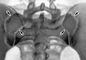

Одним из наиболее информативных методов исследования крестцово-подвздошного сустава является рентгенография. На прямой рентгенограмме суставные поверхности крестца и подвздошных костей проецируются в виде вытянутых овальных теней. По их краям видны дугообразные полоски просветления, соответствующие суставным щелям (рис. 3). На рентгенограмме в одной из косых проекций суставная щель представлена полосой просветления, края которой соответствуют суставным поверхностям крестца и подвздошной кости (рис. 4). Рентгенологическое исследование крестцово-подвздошного сустава проводят после тщательного очищения кишечника с помощью клизм. Снимки делают в прямой и косых проекциях.

Для снимка обоих суставов в прямой проекции кассету помещают поперечно под поясничную область больного, лежащего на спине; верхний край кассеты располагают на уровне остистого отростка LIV. Центральный луч направляют перпендикулярно на середину кассеты. Для рентгенодиагностики травм и заболеваний крестцово-подвздошного сустава важна точная укладка больного: даже при небольшой ротации таза изображения суставов становятся несравнимыми между собой, что может привести к диагностическим ошибкам. При точной укладке щель лонного сочленения соответствует середине крестца. В связи с тем, что щели К.-л. с. расположены косо, производят также снимки в косой проекции: в положении на спине с поворотом на 15—20° в сторону, противоположную исследуемому суставу. Центральный луч направляют вертикально на участок живота исследуемой стороны, расположенный на 3—4 см латеральнее средней линии на уровне верхней передней подвздошной ости. В этих условиях суставная щель располагается по ходу центрального луча. Для сравнения рекомендуется делать косые снимки обоих суставов при идентичных условиях. Кроме снимков в прямой и косой проекциях производят аксиальные снимки. При этом исследуемый сидит на рентгеновском столе и наклоняет туловище кпереди (или кзади); кассету с пленкой располагают под тазом. Наряду с обзорными снимками по показаниям, производят также томограммы крестцово-подвздошного сустава в различных проекциях, снимки с прямым увеличением изображения.